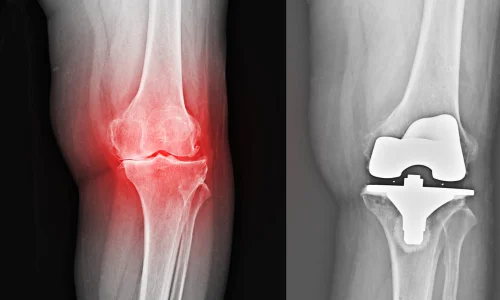

Replaces worn knee surfaces with artificial components to reduce pain, stiffness, and walking difficulty. Helps restore mobility and provides long-lasting relief in advanced arthritis cases.